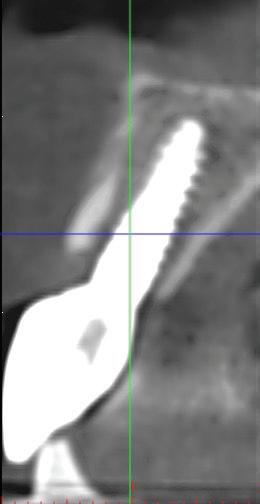

De asemenea, trebuie evaluate anual modificările radiografice. În ședința de inserție a restaurării, se înregistrează o radiografie bitewing standardizată pentru a permite evaluarea anuală a modificărilor osoase din jurul implantului. Remodelarea osului alveolar în primul an este bine documentată și depinde de tipul de implant utilizat; cu toate acestea, nu ar trebui să apară apical de primul filet al implantului. Prin urmare, este importantă abilitatea de a vizualiza filetele implantului pe radiografii. Modificările pierderii osoase de 2 mm sau mai mult după primul an reprezintă un semn de periimplantită. De îndată ce pierderea osoasă este recunoscută, pacientului trebuie să i se recomande terapia imediată pentru a opri procesul de boală.

Utilizarea platform-switch și-a dovedit eficiența în sistemele moderne de implanturi. Însă acum, zona conică inversată oferă mai mult spațiu și un suport mai bun de aderență pentru țesutul dur și moale decât formele cilindrice ale implanturilor, așa cum cum se poate vedea în imaginea următoare.

Suprafața microstructurată din zona conică inversată sprijină atașarea osului și a țesutului conjunctiv. Atunci când marginea acesteia este poziționată subcrestal, este recomandată utilizarea unui material de augmentare (xenogrefă sau os autolog) care poate preveni dezvoltarea țesutului moale în zona conică inversată și poate oferi suport pentru o mai bună osteointegrare.